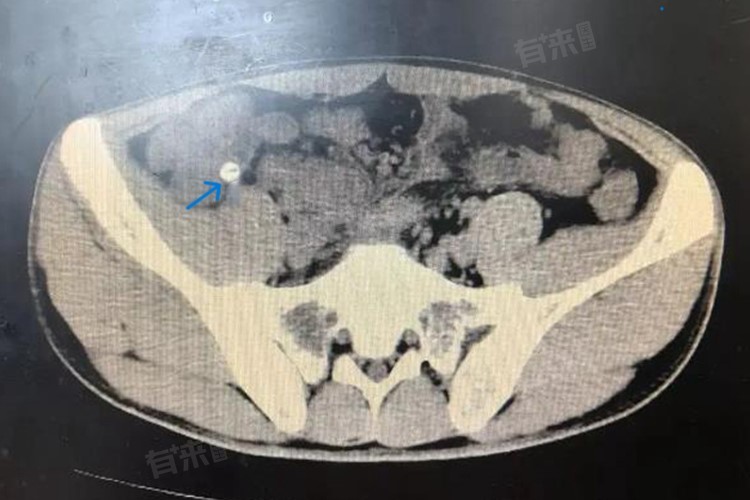

- CT检查在显示阑尾粪石方面更具优势,可精准呈现粪石大小、位置,以及阑尾周围组织受累状况,为诊断复杂病例提供关键信息。血常规检查通过检测白细胞计数、中性粒细胞比例等指标,判断是否存在炎症,辅助诊断阑尾粪石引发的阑尾炎。